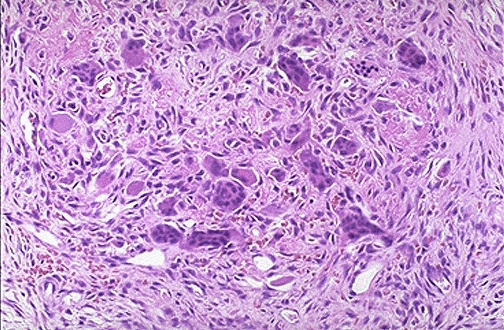

| The center of the "brown tumor" contains osteoclasts and mononuclear cells and fibroblasts with focal hemorrhages. The hemosiderin from the hemorrhage produces the grossly brown color. Such lesions are nowadays uncommon because hyperparathyroidism is treated before such lesions develop. |